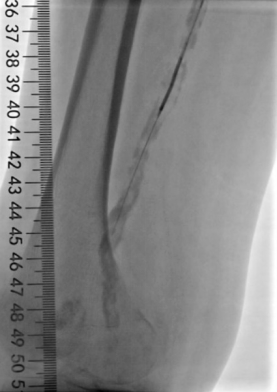

5. 选择6*60mm Shockwave冲击波球囊处理股腘动脉

6. 股浅动脉下段置入6-150mm载药支架,于股浅动脉中上段置入6-220、 6-150mm载药球囊扩张

本例患者股浅动脉重度闭塞,股浅远端重度钙化病变近收肌管,利用Shockwave冲击波球囊获得满意的管腔准备后联合使用DES,为保障远期通畅植入支架,支架膨胀形态理想。

我国患者股浅动脉又多以长段闭塞病变为主,为保障远期通畅率,支架的植入往往不可避免,此时如何优化支架膨胀则至关重要。利用“聚焦式”的冲击波能量作用于重度钙化环最薄弱处,在低压下安全打开钙化斑块,尤其是限制血管床弹性的环形钙化,可有效增加管腔顺应性,减少弹性回缩。